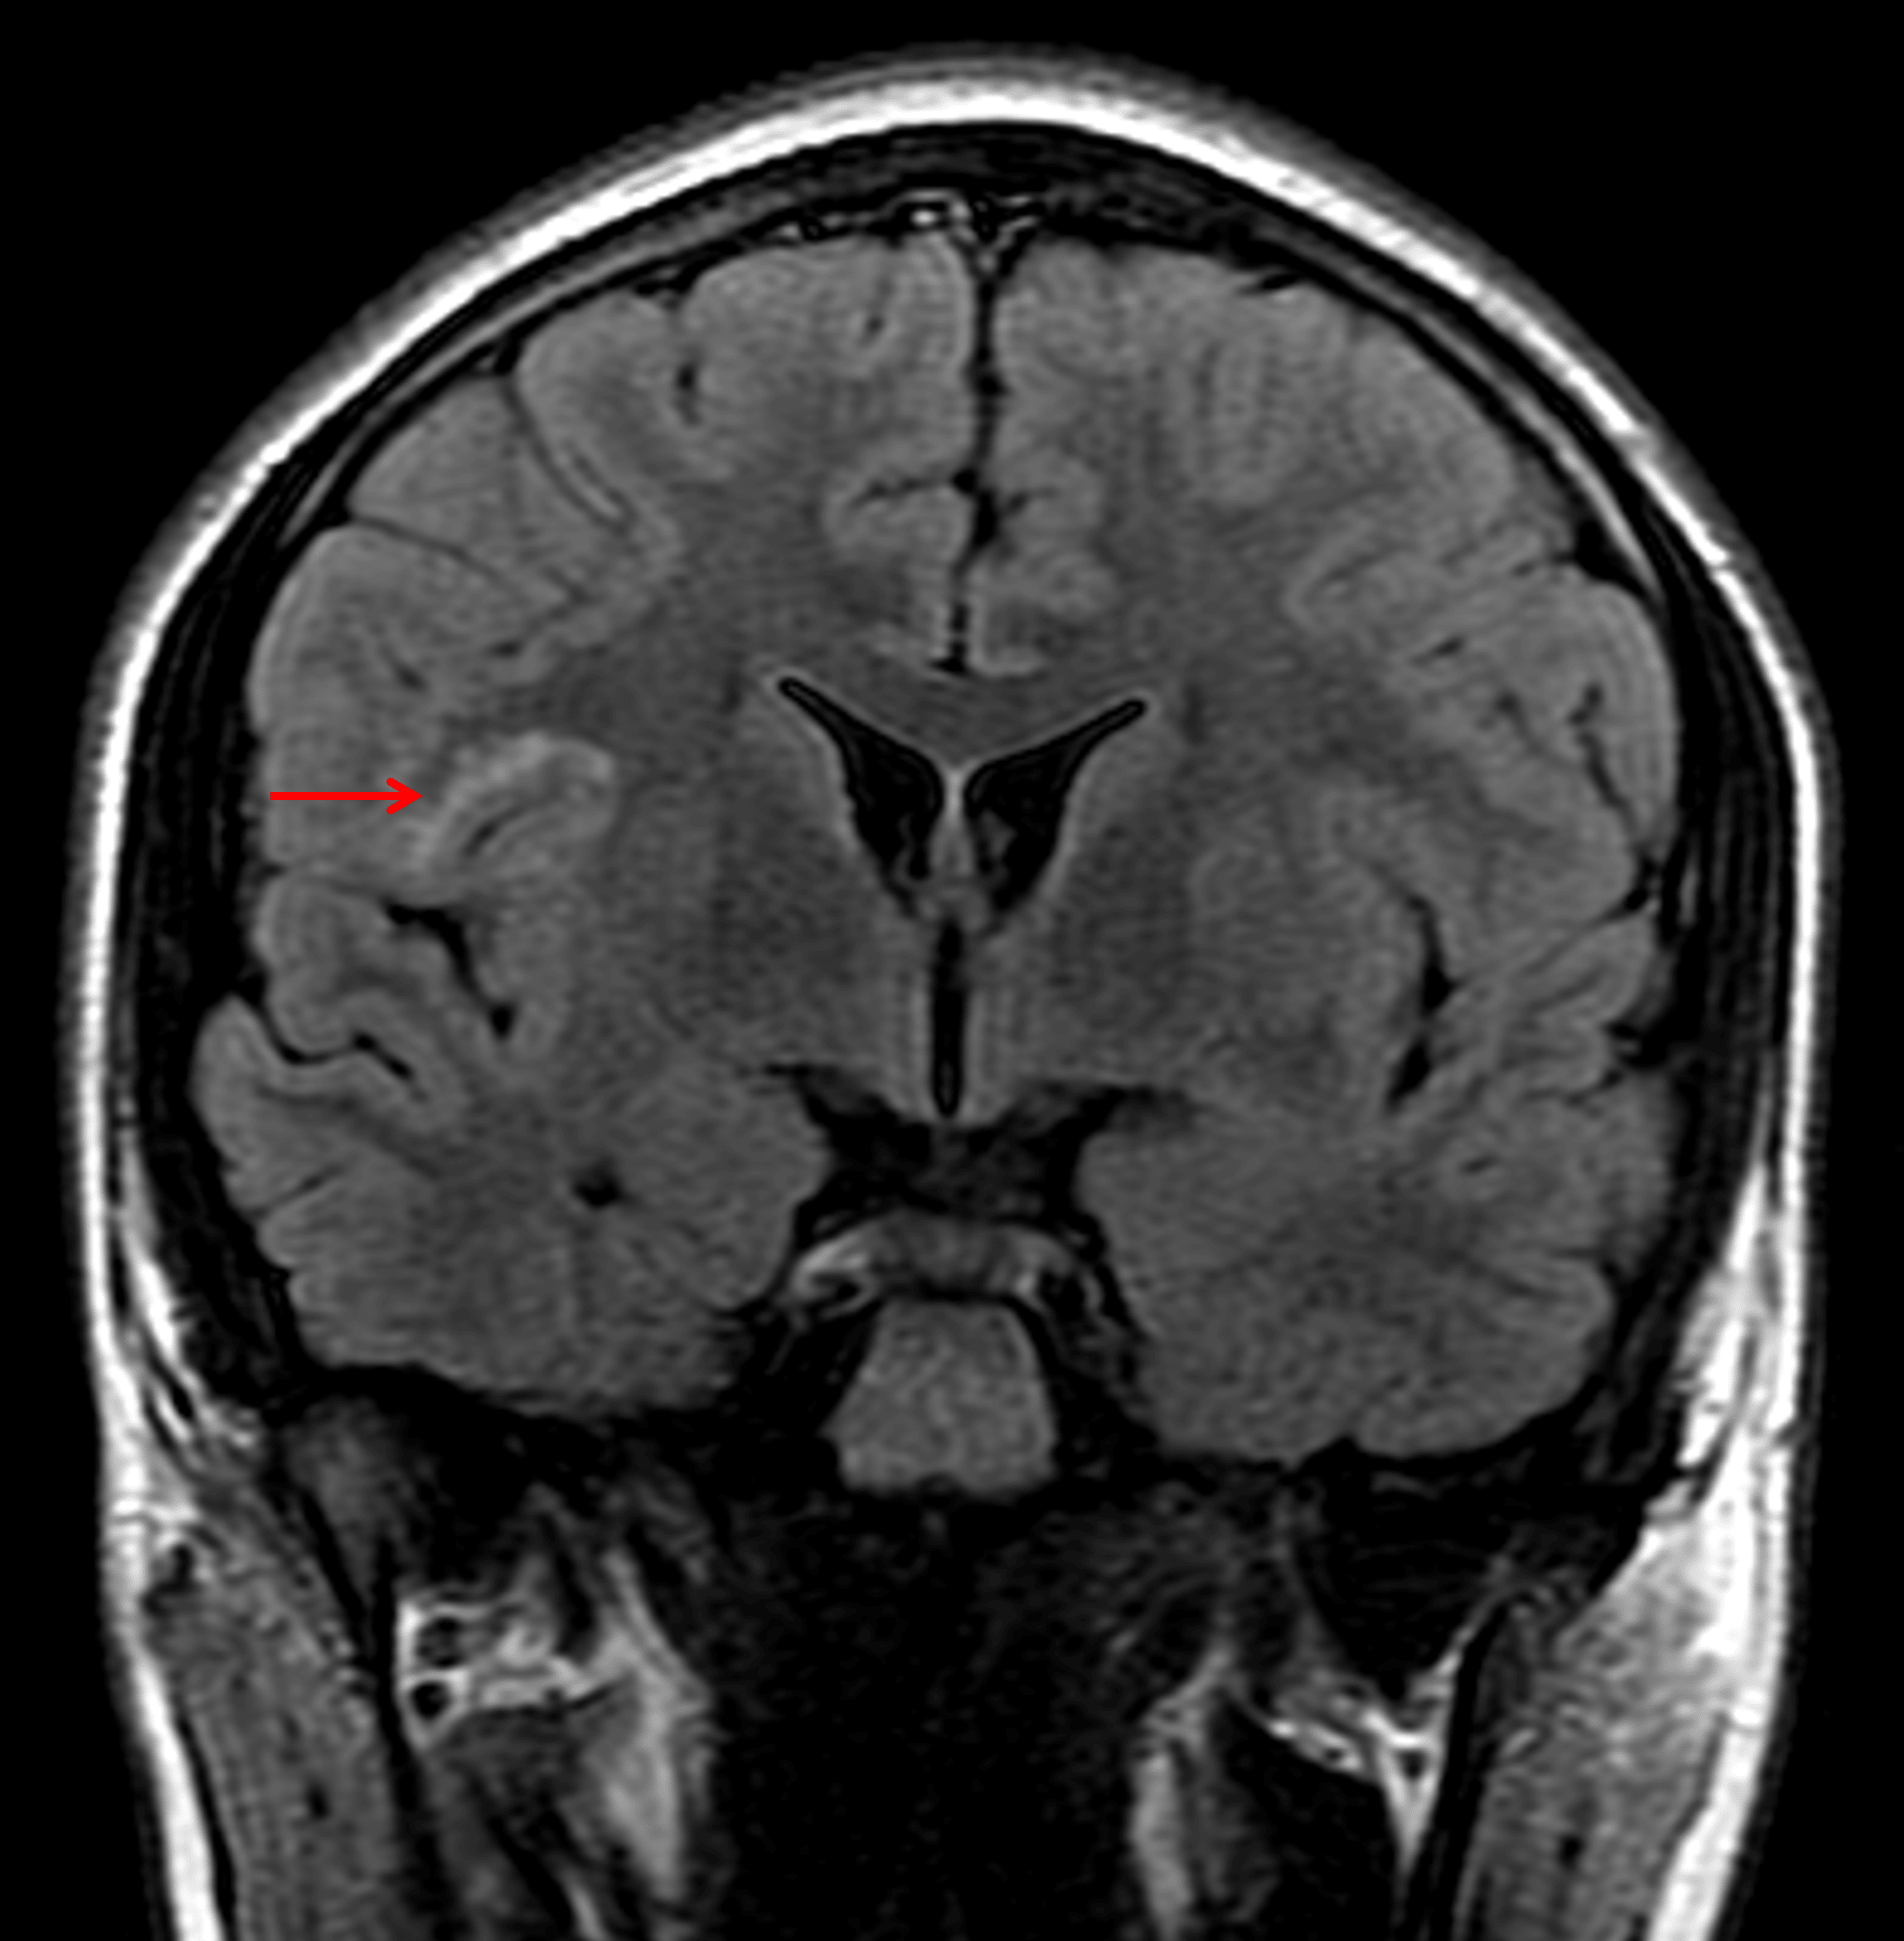

This lesion remains hyperintense on FLAIR (red arrow).